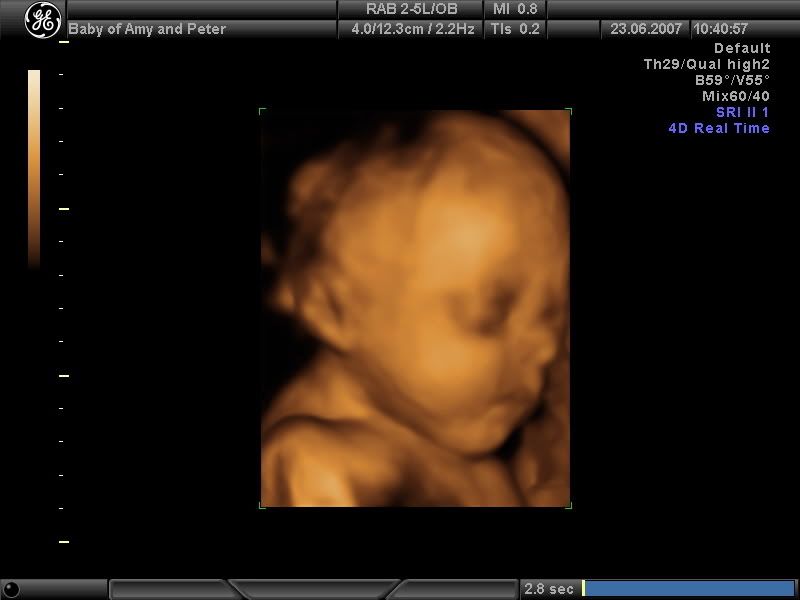

Completely O/T we splurged a bit at the weekend and paid for a 4d scan of our new bundle of joy and we found out we're having another boy

He's the image of his big brother, I'm going to have difficulty telling them apart

Boo - he's absolutely gorgeous - how long until your due date now?Total Debt 13th Sept 2006 (exc student loan): £6240.06 :eek:

Boo your baby looks lovely